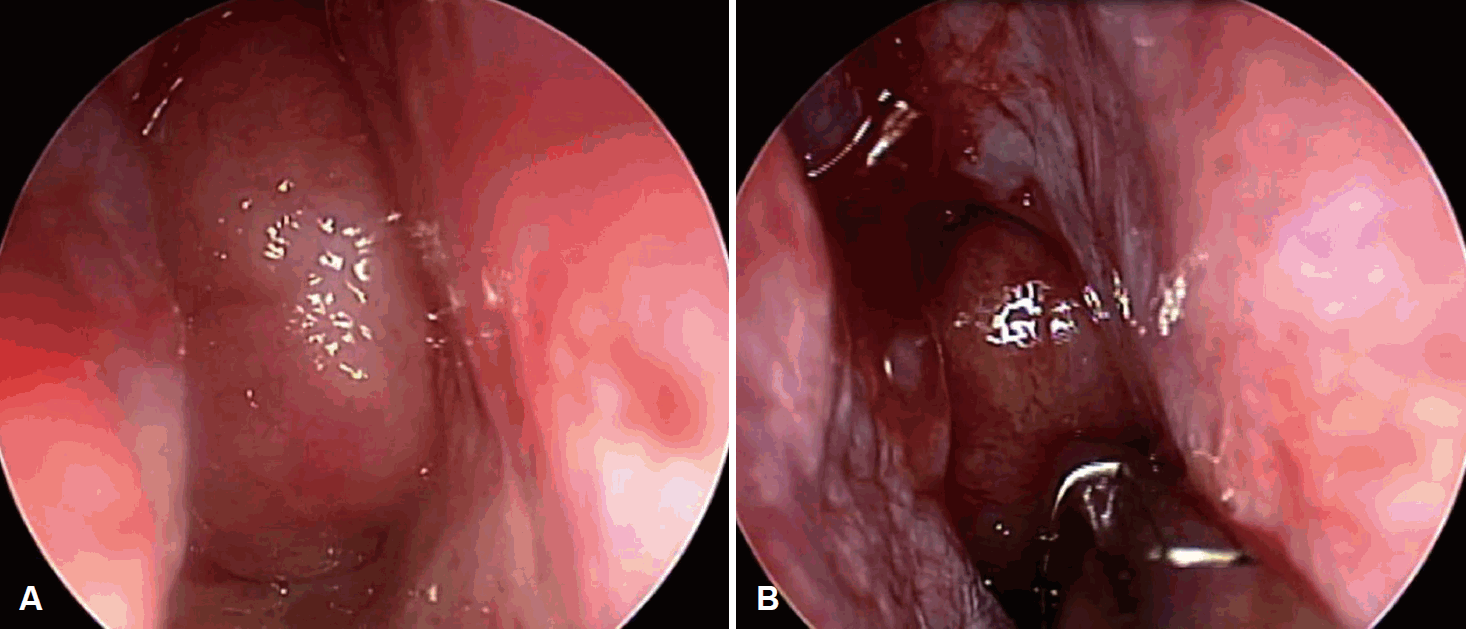

45세 남자 환자가 내원 20년 전부터 시작된 양측 코막힘 주소로 내원하였다. 콧물 및 후비루는 없었으나 코골이, 구호흡, 수면 무호흡증을 호소하였다. 시행한 코 내시경 검사상 우측으로 편위된 비중격 소견 및 양측 후비공을 완전히 막고 있는 부드러운 표면을 가진 비인두 종물이 확인되었다. 조영증강 전산화단층촬영 영상에서는 좌측 접형동의 부비동염과 함께 조영 증강되는 약 2.5 cm의 비인두 종물이 확인되었다. 이후 시행한 조영 증강 자기공명영상에서는 비인두 종물이 T1, T2 강조영상에서 모두 고강도 신호로 나타났으며, 조영증강 시 균질하게 조영 증강되어 양성 림프구 증식증, 림프종, 악성 종양 등이 의심되었다(Fig. 1). 이에 부비동 내시경 수술, 비중격 교정술 및 비인두 종물 절제 수술을 계획하였다. 수술장 소견상 매끈하고 둥근 모양의 비인두 종물이 확인되어 내시경적 절제술을 시행하였고 수술 시 종물을 겸자로 잡으면 잘 부서지고 출혈이 잘 되는 소견이 있어 piece meal로 제거하여 지혈하였다(Fig. 2). 수술 과정에서의 특별한 합병증이나 수술 후 후유증 없이 잘 회복되어 퇴원하였다.

Endoscopic findings of the nasopharyngeal mass. A: Nasopharynx was filled with round and smooth mass. B: Mass was easily bled during the excision.